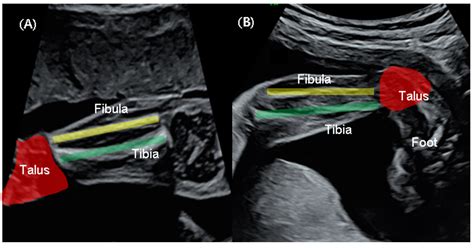

Clubfoot, medically known as congenital talipes equinovarus, is a deformity in which an infant’s foot is turned inward and downward. It affects the muscles, tendons, and bones of the foot. While the exact cause is often unknown—a combination of genetic and environmental factors—it is one of the most common birth defects involving the musculoskeletal system.